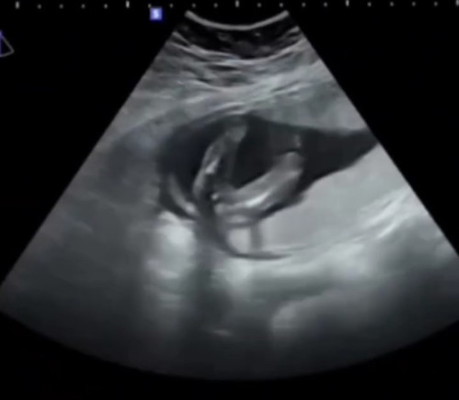

มีใครดูออกไหมคะ ว่าน้องเพศไหน แล้วจะเปลี่ยนแปรงไหม ตอนนี้ 16w2d ค่ะ ลุงหมอบอกว่า น้องน่าจะเป็น ผู้หญิงค่ะ แต่ยังไม่ชัวร์ 😍☺️